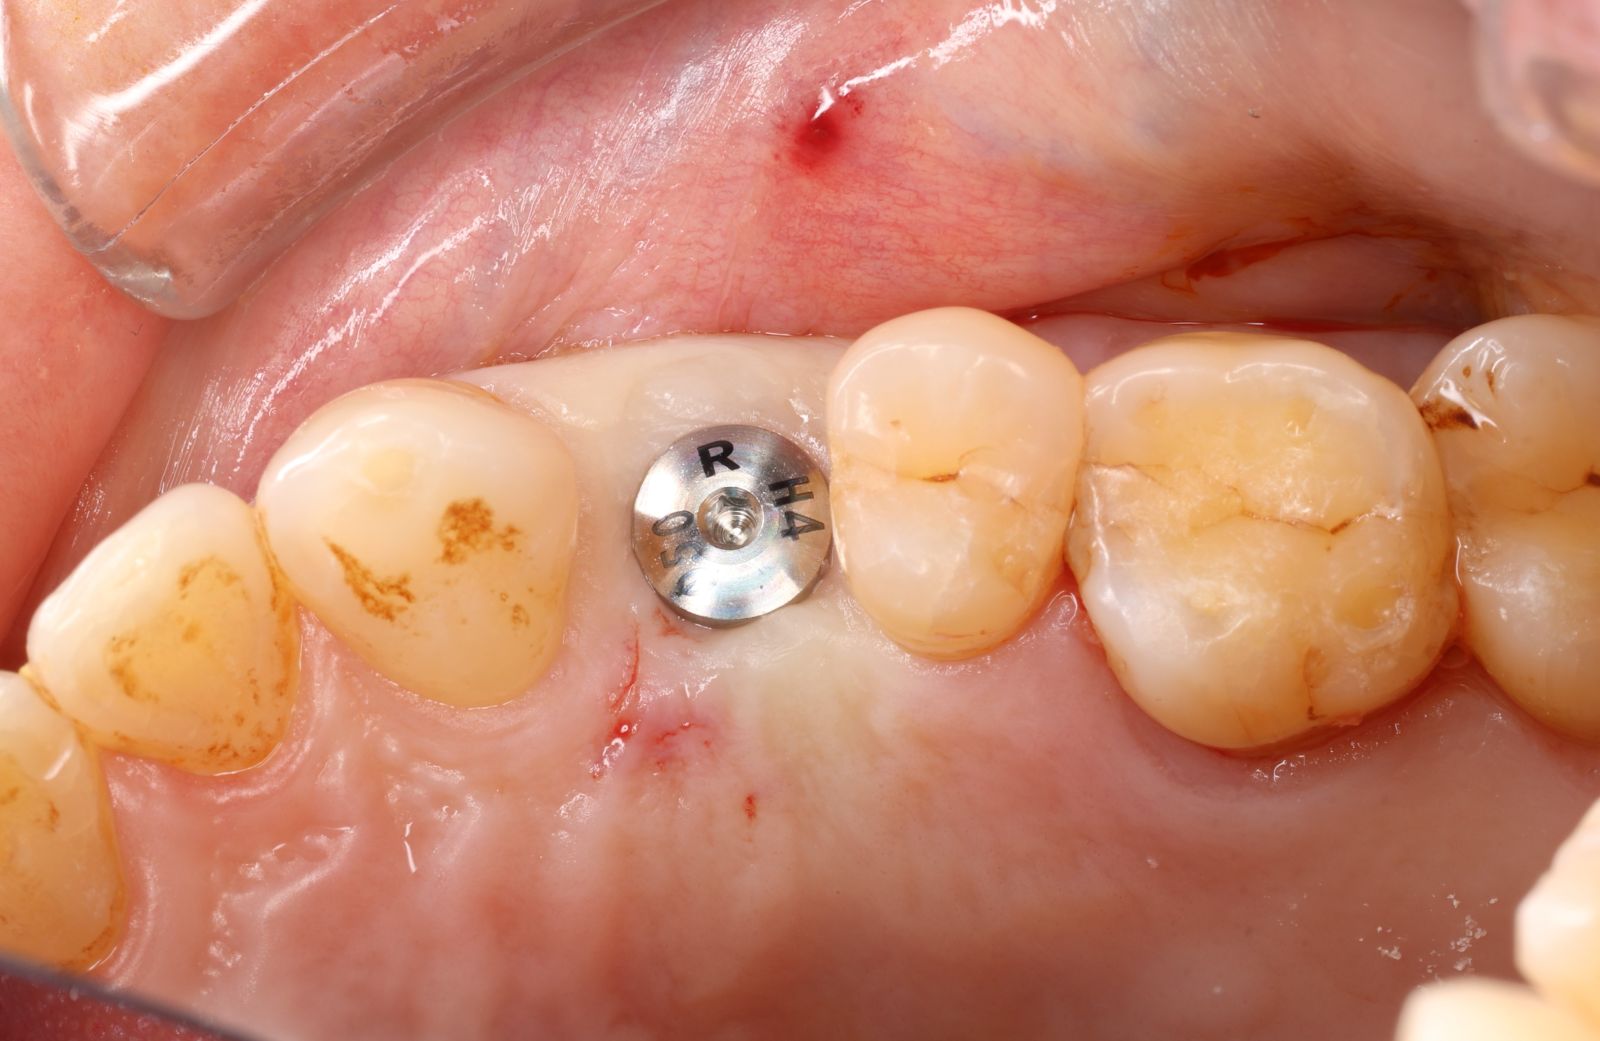

【 案 例 三 】

- 手術過程,在植入植體前先用導板定位,確認植牙位置及角度。使用導板讓傷口範圍縮小。

- 手術後傷口小無需縫合,也不用再來拆線,幾乎不會腫脹出血,術後恢復期舒適快速!

- 待3.4個月後裝上全陶瓷牙冠完成植牙療程。整個療程過程輕鬆。